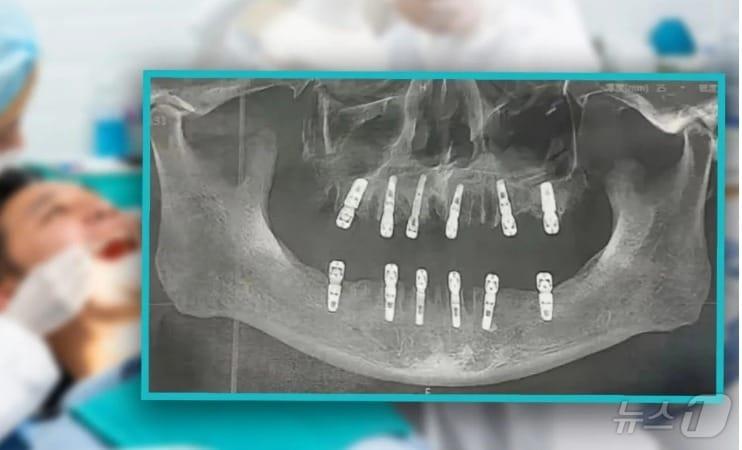

관련 시각물 - SCMP 갈무리관련 키워드발치임플란트치과지구촌화제박형기 기자 엔비디아 PER 45-테슬라는 302…엔비디아 저가 매수할 만미증시 연일 하락하는데 암호화폐는 랠리, 상승세로 방향 잡은 듯관련 기사"턱뼈 괴사 예방, 골다공증 주사 중단이 해법"…위험 '절반' 뚝임플란트 보장, 집에서 발치·사랑니는 안된다…치아보험금 '○X 체크'독거노인 구강 건강 돌본다…서울대치과병원, 이동치과 '무료 진료'"102세에 자연치아 23개"…건치 어르신의 구강건강 비결은?잘 씹히는, 튼튼한 '임플란트' 5가지 조언은?…"정기검진 권장"